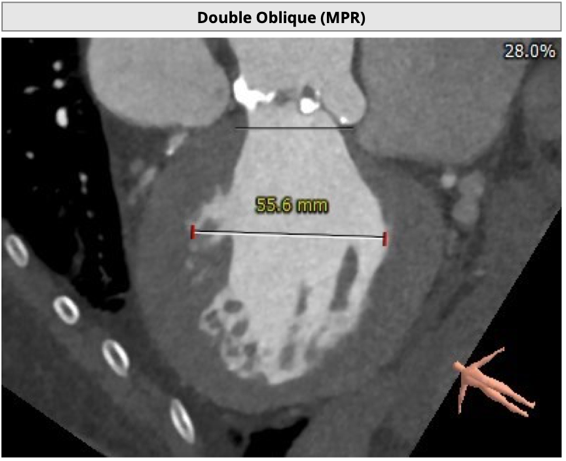

主动脉根部评估

CT 数据显示该患者为Type1型二叶式主动脉瓣

主动脉瓣瓣环周长76.8mm,周长径24.5mm;

LVOT 周长 86.1mm,周长径27.4mm;

SOV:32.3mm*34.5mm*33.7mm;

STJ 周长 100.6mm;

瓣叶严重粘连增厚,瓣叶钙化明显,HU850:1448.3mm³。

左冠开口高度8.6mm,右冠开口高度15.0mm,左冠高度偏低,左冠瓣瓣尖钙化明显,根据瓦氏窦内径和瓣叶长度综合判断,左冠存在较高堵塞风险;左心室后壁增厚。